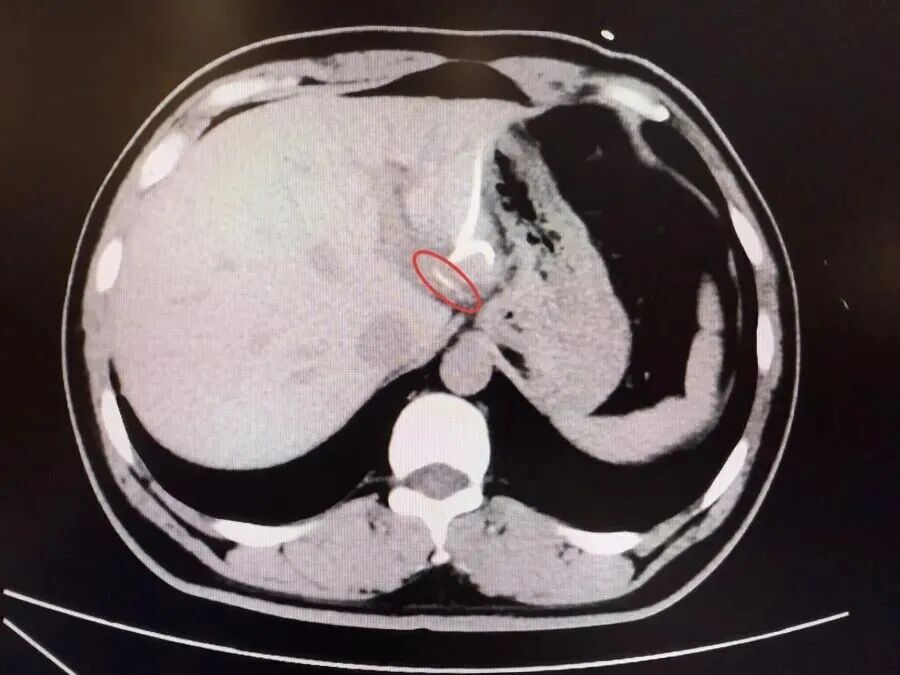

半月前,37岁的李先生(化名)误吞鱼刺却未察觉,数天后出现腹痛、高热(达40℃)等症状,当地医院诊断为“肝脓肿”,治疗后症状反复,CT检查才发现肝脏左叶有鱼刺——其已穿透胃壁入肝引发感染,十分危险,当地医生评估后认为,要彻底清除异物,需要进行左半肝切除手术,这让李先生难以接受。

为寻求更精准、微创的治疗,李先生转至复旦大学附属中山医院内镜中心。“鱼刺位置非常凶险,就在贲门旁刺入左肝,紧贴大血管。”接诊的周平红主任指出,腹腔感染粘连严重,手术难度极高。